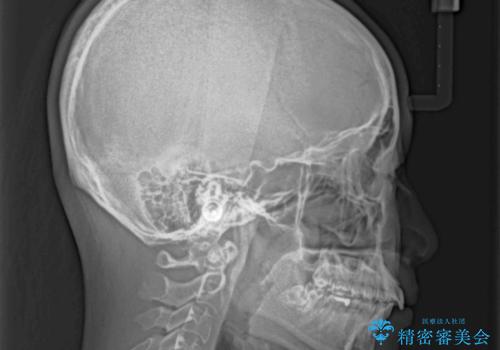

- 変色した前歯と突出した口元を気にして来院された患者様です。

口元の突出感はインビザラインにより歯列を整え、その後に、前歯をオーダーメイドタイプのオールセラミッククラウンにて補綴治療することとしました。

長時間のマウスピース装着と、患者様自身でのゴムかけに協力いただき、口元の突出感をしっかりと改善することができました。